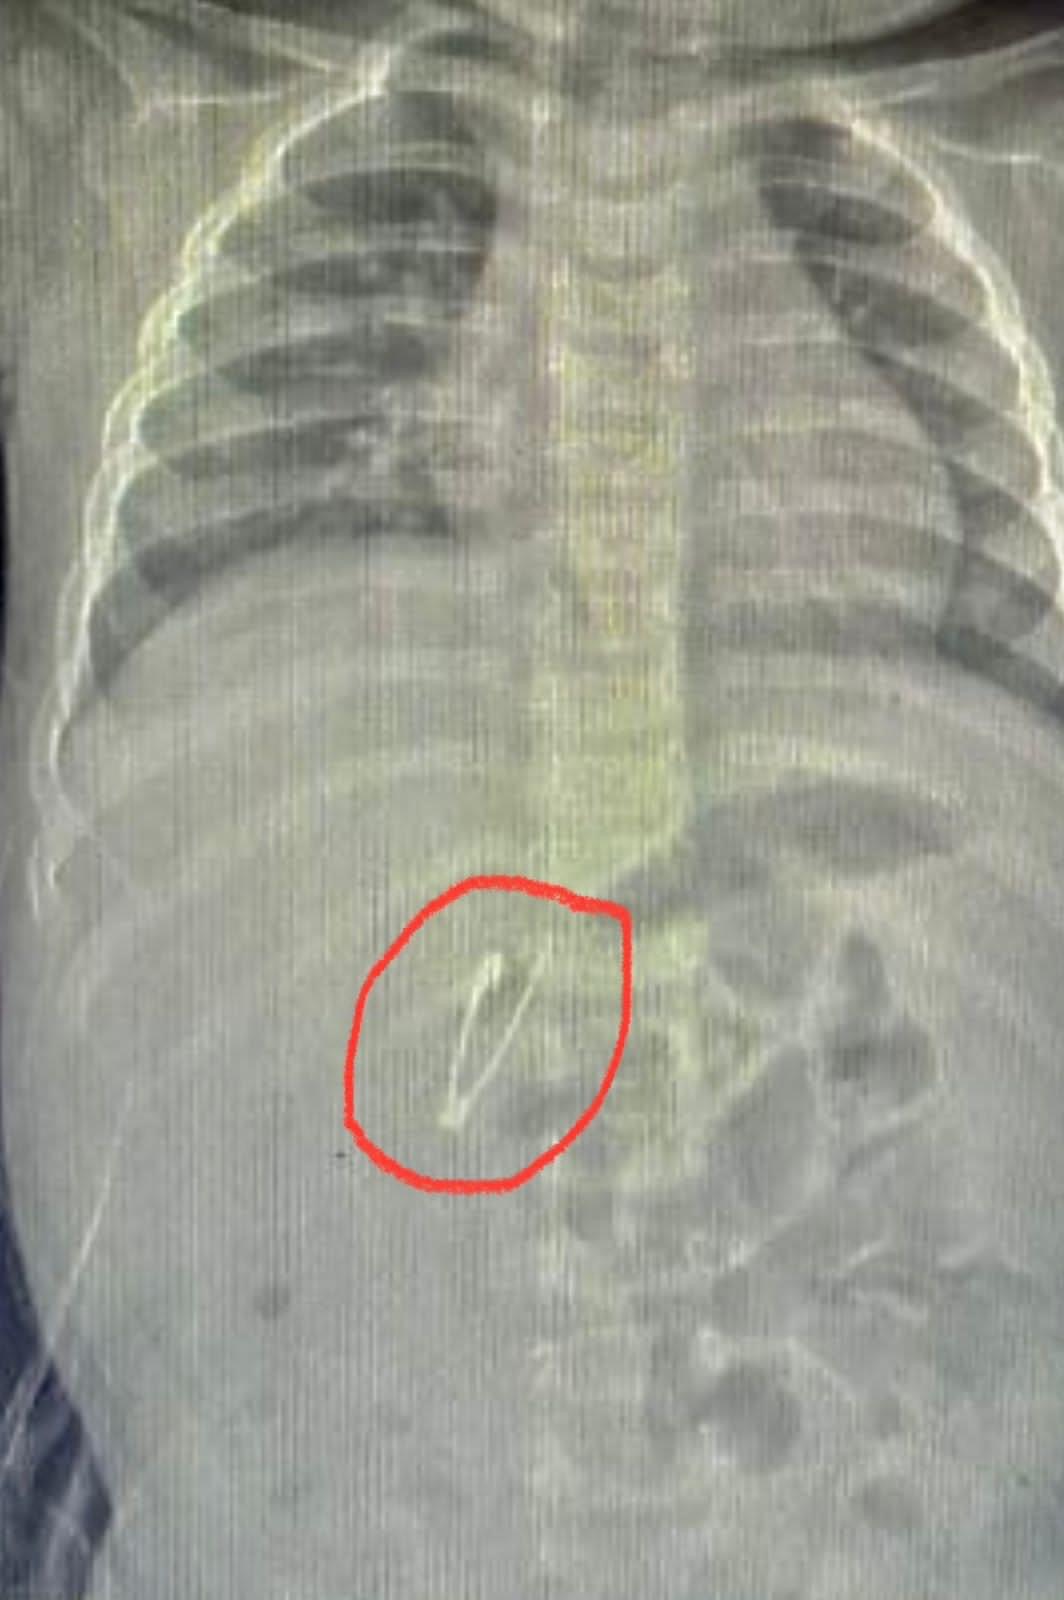

وبينت الأشعة وجود الدبوس في الجزء الأول من الاثني عشر وانغرس طرف الدبوس المدبب فى جدار الأمعاء ولم يكن هناك حلول مطروحة سوى استخراجه عن طريق المنظار والذي يحتاج إلى مهارة عالية جدا، نظرا لأن عمر الطفل 7 أشهر فقط.

وتعاملت الدكتورة إسراء زينهم مدرس مساعد طب الأطفال مع الحالة بحرفية شديدة ومهارة عالية تم خلالها استخراج الدبوس بسلام دون حدوث أية مضاعفات.